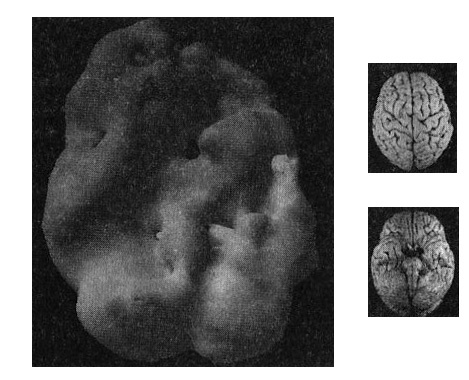

Рис. 10.3 Вид снизу

Снимок мозга 16-летнего подростка, упавшего с велосипеда и серьезно повредившего лобную кору с левой стороны и левую височную долю